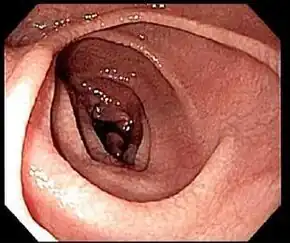

Endoscopic still of duodenum of person with coeliac disease showing scalloping of folds and "cracked-mud" appearance to mucosa

Most people with coeliac disease have a small intestine that appears to be normal on endoscopy before the biopsies are examined. However, five findings have been associated with a high specificity for coeliac disease: scalloping of the small bowel folds (pictured), paucity in the folds, a mosaic pattern to the mucosa (described as a "cracked-mud" appearance), prominence of the submucosa blood vessels, and a nodular pattern to the mucosa.[96]